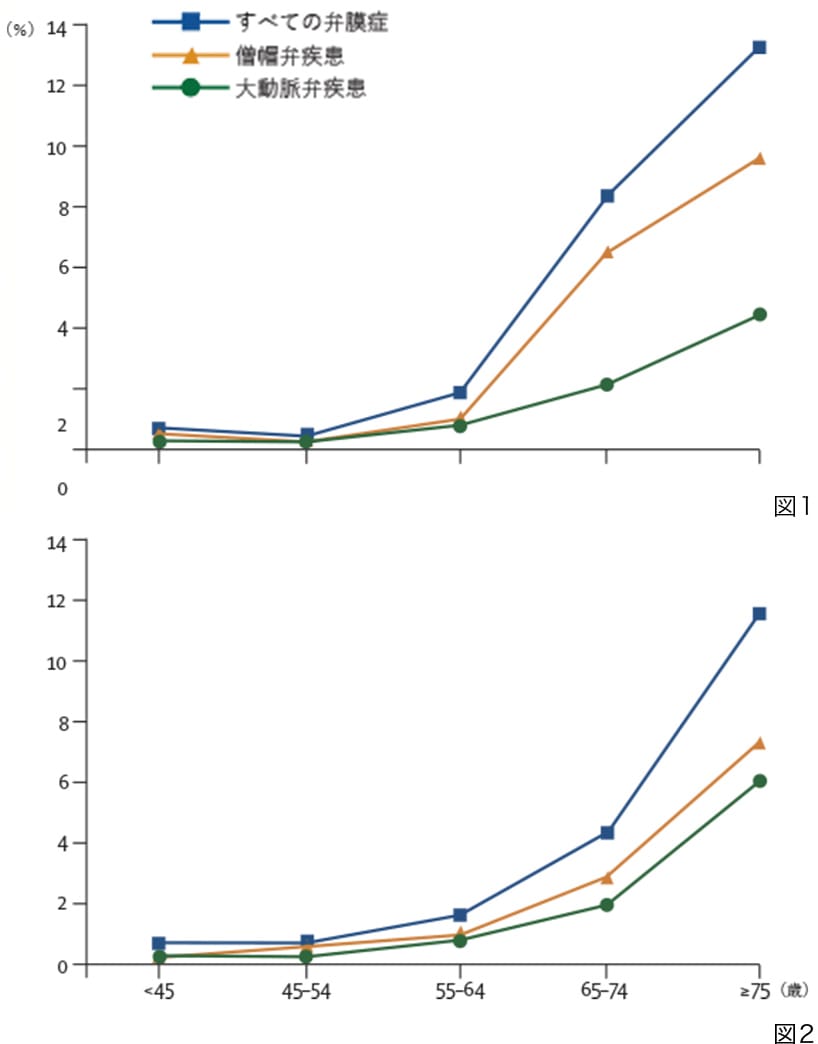

心臓弁膜症は年齢が上がり、高齢になればなるほど増加する病気です。そのなかでも僧帽弁疾患は最も多い心臓弁膜症であり、すべての弁膜症の大きな部分を占めています。

米国の統計では75歳以上の9.3%に存在するという報告もあります(図1)。

本邦における心臓弁膜症の手術件数も、高齢化社会に伴い増加の一途をたどっています(図2)。

図1:米国人口ベース調査

図2:米国ミネソタ州オルムステッド郡調査

*Nkomo VT, et al. Burden of valvular

heart diseases: a population-based study.

Lancet. 2006;368:1005-11.